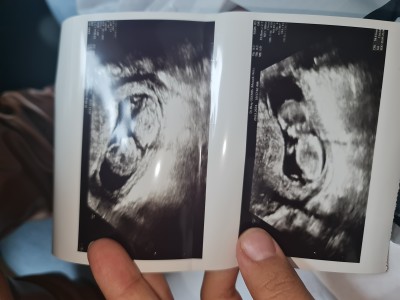

Kizlar rica etsem cinsihet tahmini yapabilir misiniz 12 haftadayim

Çatık kaslı erkek gibi geldi sinirli bı bebiş;))) Allah bağışlasın cnm

Kız bebek bence

Bence erkek öğrenince yazarsın artık:)

Erkek bacım erkek